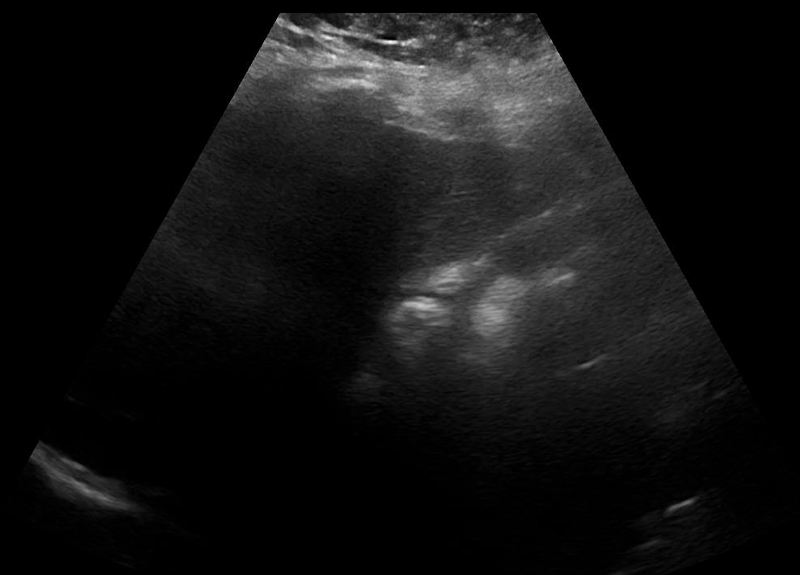

POCUS transabdominal revealed no free fluid in hepatorenal space (image 1), and the uterus without an intrauterine pregnancy (image 2) but with pelvic free fluid (image 3). The left adnexa revealed a gestational sac with a yolk sac (image 4), diagnostic for an ectopic gestation.

Image 3: Sagital pelvic view nows show free fluid posterior to the uterus and again a very concerning adnexal structure concerning for ectopic pregnancy.